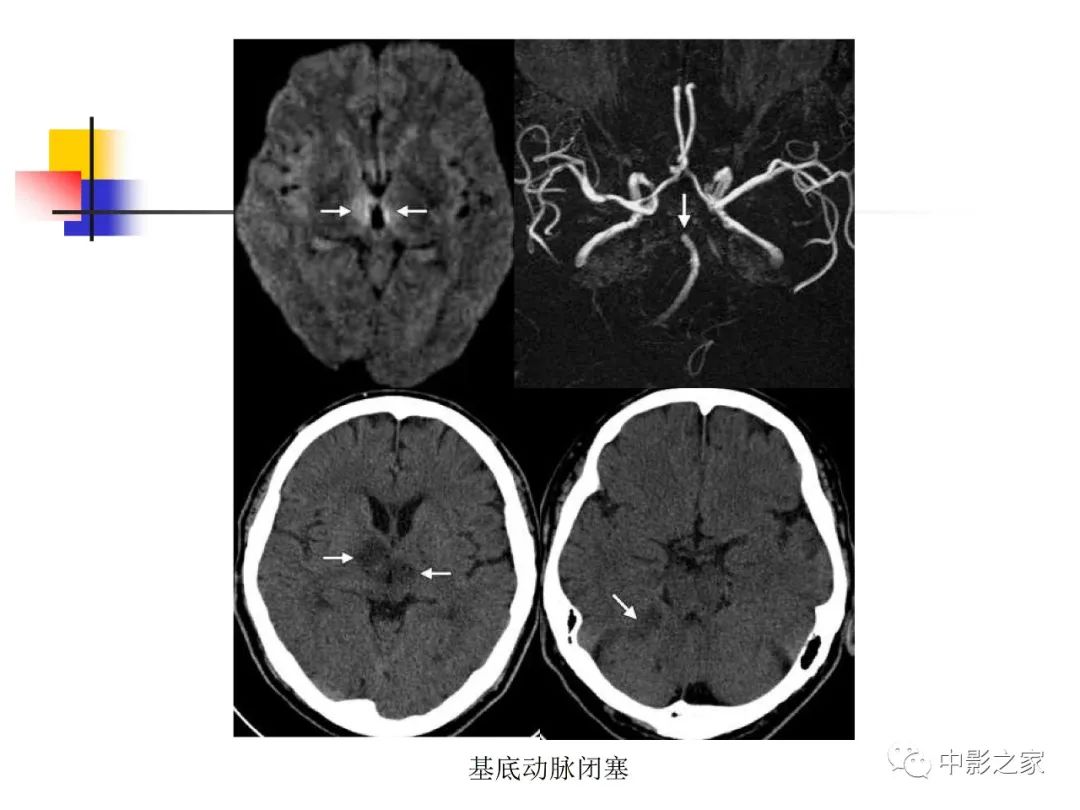

双侧基底节、丘脑病变影像学表现

作者:天津医科大学总医院 张云亭